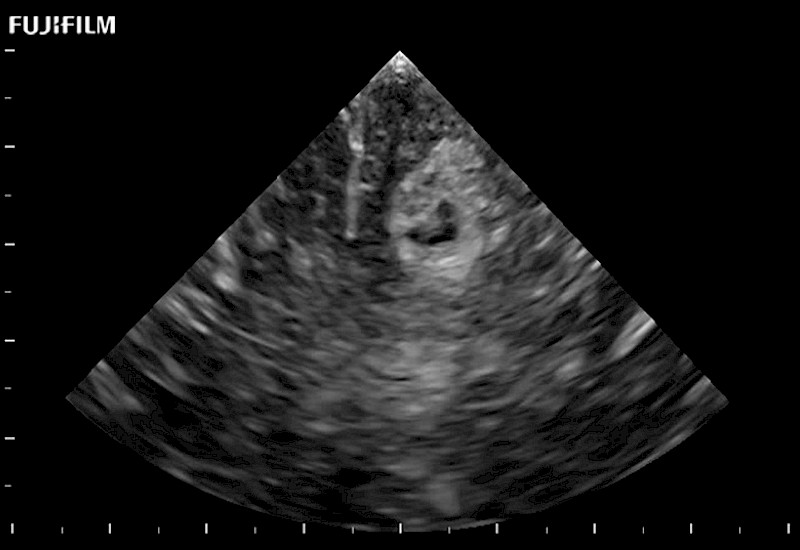

Fujifilm Healthcare understands that neurosurgeons demand excellence in their operating rooms — from their staff and the equipment they depend on. Fujifilm Healthcare's dedication to neurosurgery provides outstanding ultrasound technology, professional support, and the specialized tools necessary to best perform comprehensive real-time ultrasound imaging.

For precise neurosurgery ultrasound imaging, Fujifilm Healthcare offers premium level solutions that include:

Extraordinary high-resolution digital imaging

Exceptional transducers

for use during: Cranial guidance, Burr-Hole guidance, Spinal Cord guidance, Pituitary guidance, Micro-Surgery guidance

Multi-Parametric imaging modalities

Our dedication to neurosurgery allows us to offer superior image quality, outstanding system reliability and intuitive use of cutting edge technology.